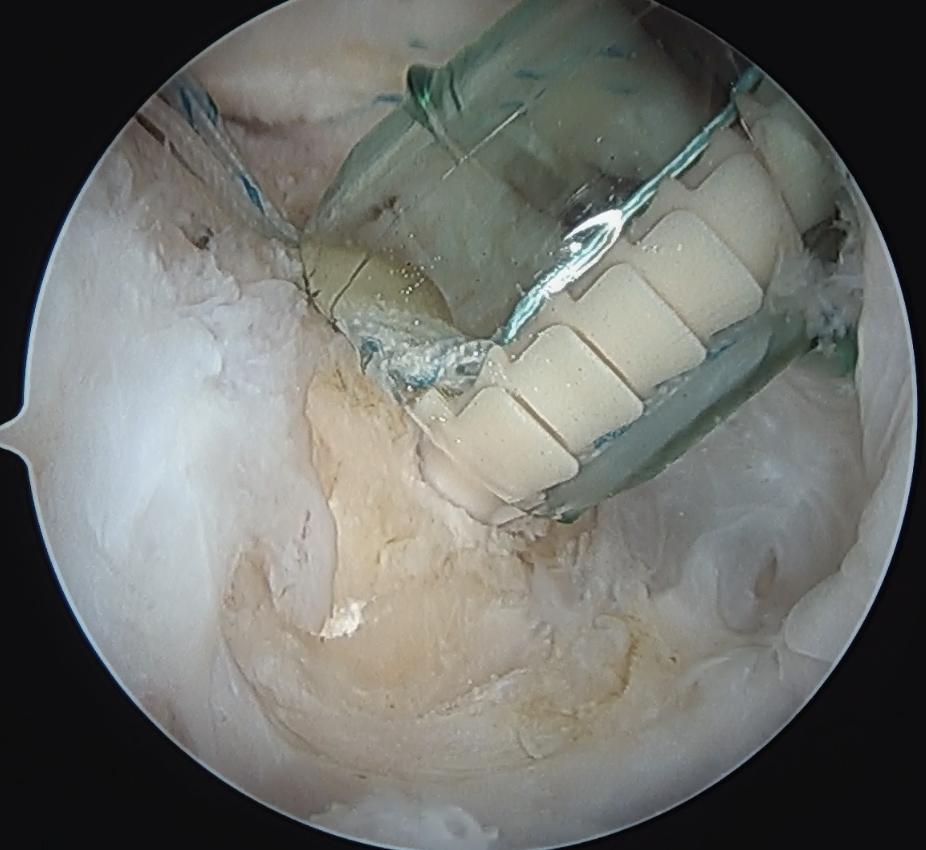

Trans-osseous equivalent / suture bridge

- cross sutures from medial row to lateral row

- increase contact between cuff and footprint

Double row / suture bridge

- use medial row sutures

- secure in knotless lateral row anchors